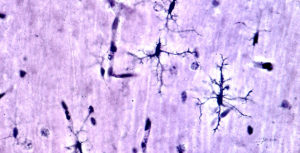

Perché i neuroni che formano la memoria sono vulnerabili all’Alzheimer

Immagine: Credit: Rockefeller University. Quando colpisce la malattia di Alzheimer, l’intero cervello non si sbriciola in una volta. Invece, la mente…